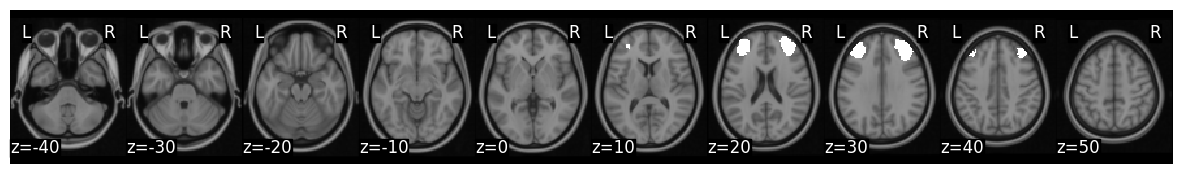

Mask is s k=50 whole brain parcellation based on neurosynth coactivations. Target ROIs correspond to left and right somatomotor cortex

mask_x[44].plot()

plt.show()